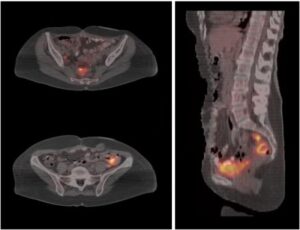

Il follow up TC (tomografia computerizzata) puo' portare benefici quando falliscono gli esami ecografici. Secondo uno studio del Massachusetts General...